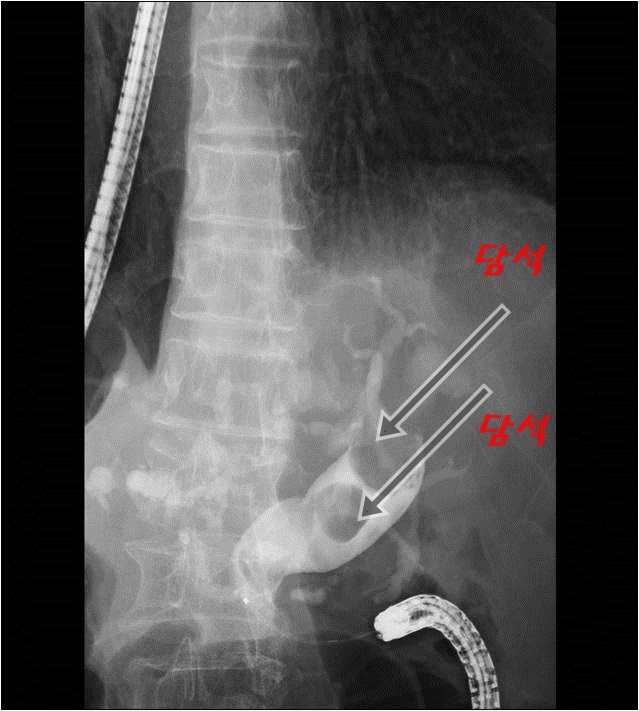

ERCP; 내시경적역행성담췌관조영술, 담석제거, ERBD, ENBD 네이버 블로그 Ercp Xray Labeled Ercp is a type of endoscopic procedure used to examine and treat the biliary tree (the gallbladder, bile and pancreatic ducts). Ercp (endoscopic retrograde cholangiopancreatography) is a specialized technique used to study the pancreas,. Despite the near ubiquitous access to advanced radiology and endoscopic ultrasound (eus) in north america, ercp still has. The normal cbd diameter of ercp imaging will. Ercp Xray Labeled.